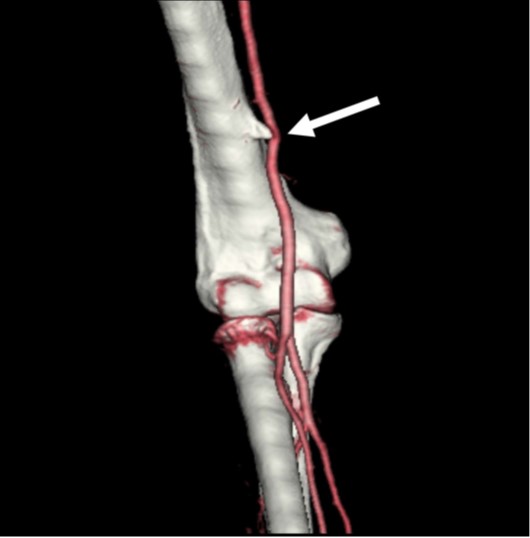

The supracondylar process, or avian spur, is a congenital bony protuberance along the anteromedial aspect of the distal humerus. It ranges in size from 2 to 20 mm and is located 5–7 cm above the medial epicondyle. The spur grows toward the elbow, unlike an osteochondroma, which is directed away from the elbow. A supracondylar process is present in 1–3% of the population, more commonly found in men and boys and on the left [2, 3]. The spur may be connected to the medial epicondyle by a fibrous band called the Struthers ligament, which creates a fibroosseous tunnel. A supracondylar process is usually asymptomatic but can fracture or cause mechanical compression of the median nerve or brachial artery, where the neurovascular bundle passes through the fibroosseous tunnel formed by the supracondylar process and Struthers ligament. The symptoms include pain, paresthesia, and weakness in the distribution of the median nerve and can be aggravated by continuous movement or local compression at the elbow [1, 2].

A supracondylar process can be seen on lateral or oblique radiographs obtained with the elbow internally rotated and can be misinterpreted as a bony exostosis or osteochondroma. However, the typical location of the supracondylar process along the anteromedial aspect of the distal humerus and direction of growth toward the joint differentiate it from an osteochondroma, which typically occurs in the metaphysis and grows away from elbow (Fig. 1A). CT angiography can show the supracondylar process and deviation, compression, or thrombosis of the brachial artery (Fig. 1B). MRI and ultrasound can depict the Struthers ligament and any compression on the neurovascular bundle. Surgical decompression is usually the preferred approach over conservative treatment of patients who have symptoms [1–8].